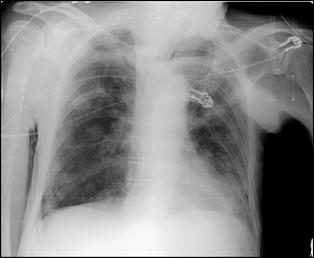

Cele mai multe metasteze la distanta, provocate de tumorile vezicale maligne, sunt localizate in plamani si in oase. Diagnosticul acestora se face prin: radiografii toraco-pulmonare, radiografii osoase sau scintigrame osoase (evidentiaza metastazele osoase cu 9-12 luni mai devreme decat expresia evidenta a acestora pe radiografiile standard).

dreapta Figura 45. Metastaze pulmonare multiple dintr-un carcinom vezical

Figura 4 Radiografie toraco-pulmonara cu metastaze pulmonare multiple

dintr-un carcinom vezical infiltrativ

Figura 47. Radiografie toraco-pulmonara cu metastaze pulmonare multiple dintr-un carcinom vezical infiltrativ.